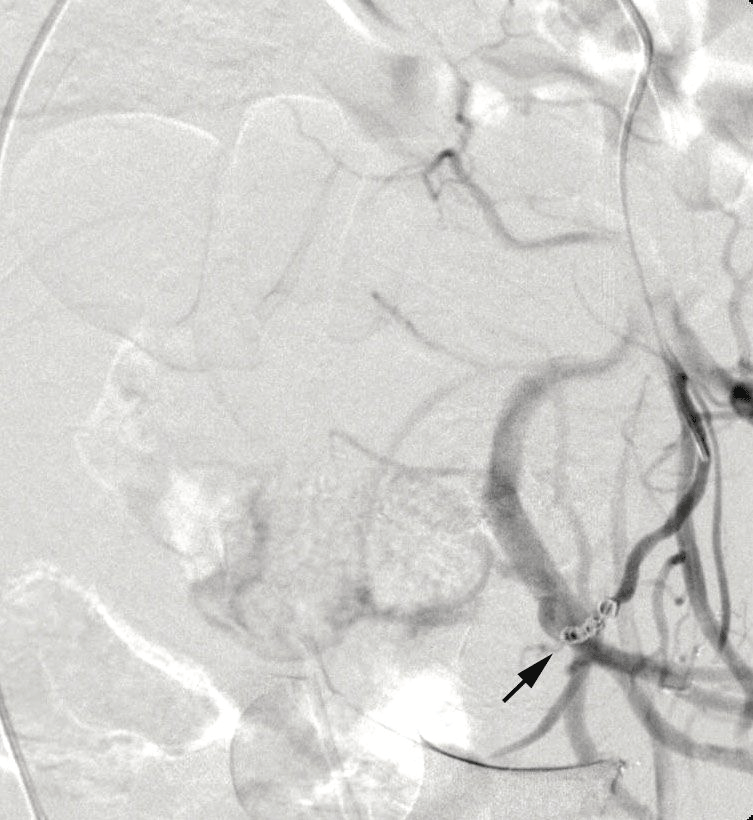

Angiographic control performed during procedure showed an important active bleeding from the pseudoaneurysm and so cyanoacrylate 1 ml was injected before metallic spirals to achieve complete embolization (Figure 1,2).

Figure 2: Left UAP embolisation

View Figure 2